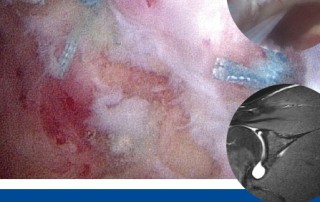

Als geladener Referent und Instruktor nahm PD Dr. med Frank Martetschläger beim internationalen Schulterkurs der European Society for Sports Traumatology, Knee Surgery and Arthroscopy (ESSKA) in York teil. Neben Vorträgen [...]